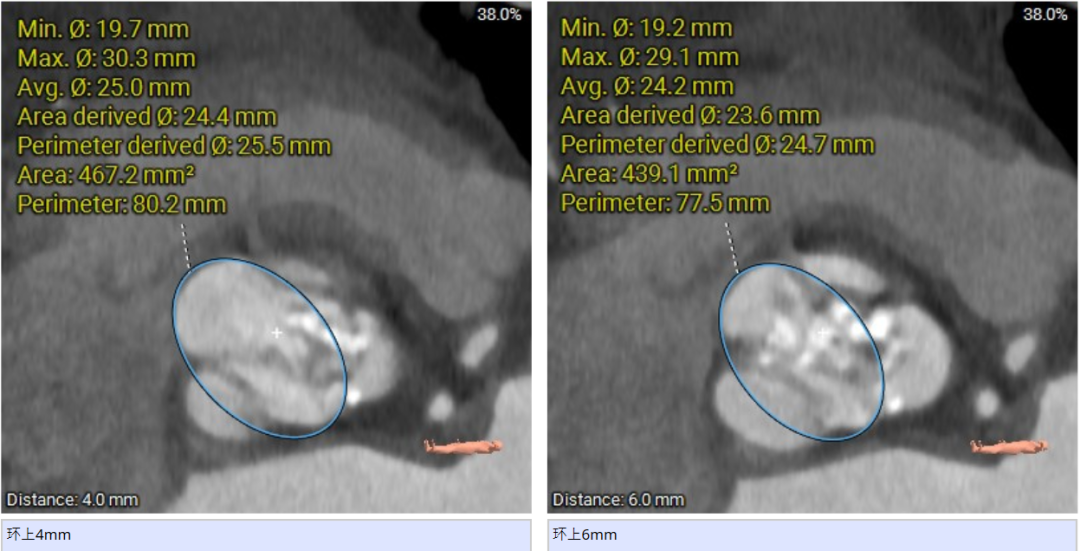

冠脉高度:

心室角度51度: